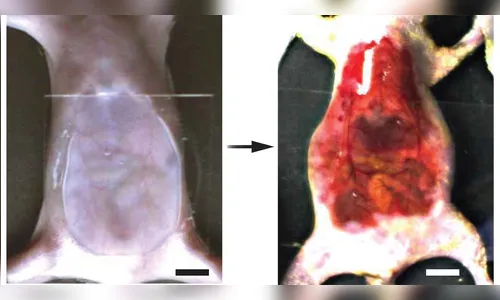

No trabalho, os cientistas conseguiram fazer com que a pele da cabeça e da barriga de camundongos vivos ficasse transparente aplicando uma mistura de água com o corante amarelo chamado tartrazina. O pelo dos camundongos foi retirado previamente. Depois de retirada a solução da pele dos animais, a transparência desaparecia.

Nos camundongos, os cientistas conseguiram observar os vasos sanguíneos do cérebro, através da pele da cabeça. Os órgãos internos dos camundongos também ficaram visíveis em seu abdômen, bem como as contrações musculares, e o caminho percorrido pelos alimentos no trato digestivo dos animais.